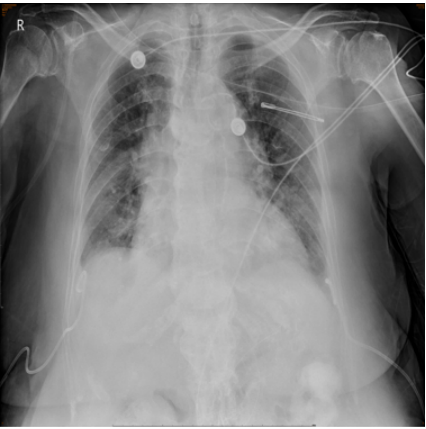

3月28日床边胸腔彩超提示双侧胸腔未见明显积液,予拔除胸腔引流管。当日胸片见图5。

图5  复查胸片(2024-03-28)